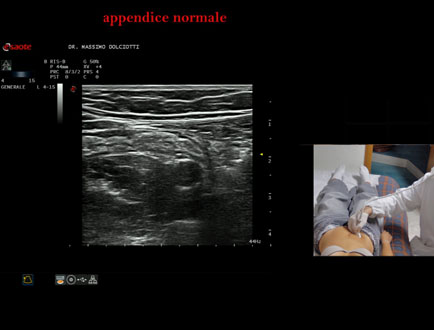

Data inserimento: 26/09/2025

Ecografia del: 12/09/2025

Strumento: Esaote MyLab Eight

Sonda: Lineare Multifrequenza 4-15 MHz

Età Paziente: F 24 anni

Motivazione dell'esame: da 3 mesi dolore al fianco destro.

Commento all'esame: le immagini ed il video documentano l'appendice di spessore normale (5,1-5,7 mm - v.n. < 6 mm).

Conclusioni: appendice normale (normal appendix).

Presentazione: Dr. Massimo Dolciotti - Ancona

Elaborazione digitale: Andrea Dini - Ancona